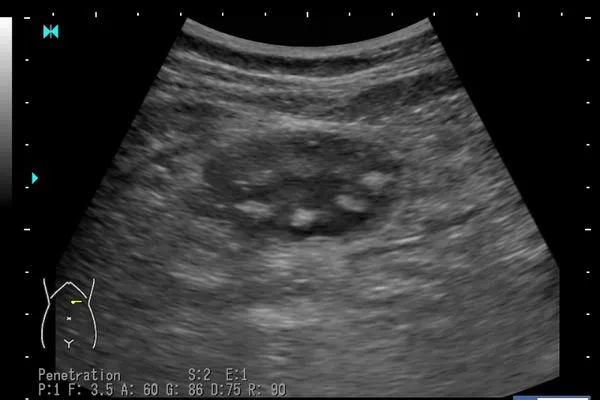

▲醫師曝珍珠不易消化,就算在胃裡也能認得出來。(圖/翻攝自Facebook/臭寶爸 - 兒科陳敬倫醫生)

台人喜歡喝手搖飲,珍珠奶茶更是不少人最愛喝的品項之一。小兒科醫師陳敬倫指出,近日來經常有家長因小孩肚子痛帶來看醫生,一照超音波,胃裡面都是「一顆一顆的珍珠,像是蓮蓬的影像」。他表示,大部分的食物到胃裡都無法區分是什麼,只有一個例外,就是珍珠奶茶的珍珠,到了胃裡還能看到一顆一顆的。

但是,「只有一個例外,珍珠奶茶的珍珠」。陳敬倫說,由於珍珠不容易消化,孩子如果吃太多,照超音波時就能在胃裡看到一顆一顆的珍珠,「像蓮蓬的影子像,如果我來命的話,我就叫它蓮蓬簽!」